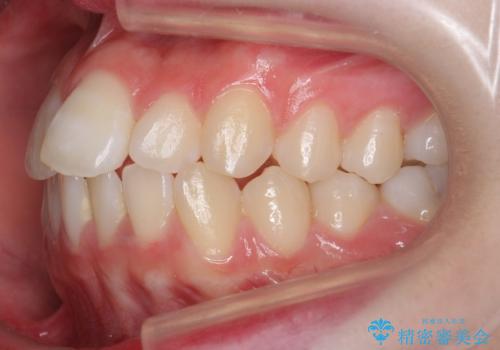

前歯のがたつき 乳歯を抜かずに矯正

- 前歯のがたつきを主訴に来院。

右上に乳歯が残っていましたが、後継永久歯がないため、抜かずに矯正しました。

乳歯の部分が反対咬合でしたが、歯列矯正で被蓋が改善するように移動させました。

右上の乳歯は移動させましたが、幸い矯正後にぐらつくこともなく、そのまま抜けるまで使うことにしました。